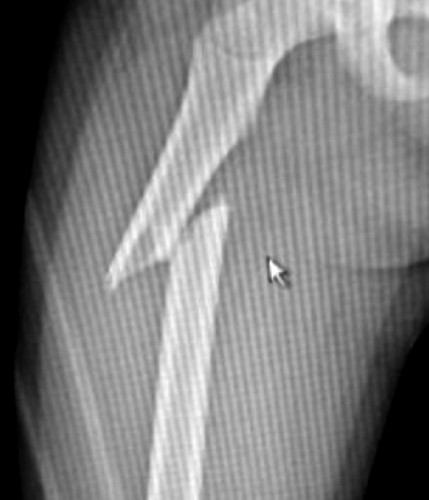

Bambina di 5 anni con frattura di femore obliqua al 1/3 prossimale

Fig. 2 rx post operatorio